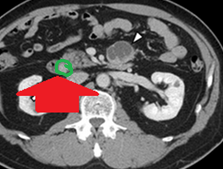

Neck SPECT/CT. Green arrow — Ectopic (within the sheath) parathyroid adenoma. Red arrow — Right common carotid artery (Courtesy Dr. V. Penopoulos)